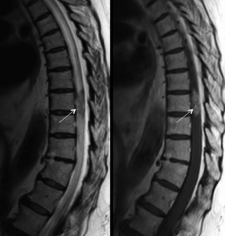

1)脊髓髓内肿瘤

是指发生在脊髓内部的一种病变,可以想象成电缆中的金属导体中混入了“杂质”。这类肿瘤主要包括室管膜瘤、星形细胞瘤、血管母细胞瘤和海绵状血管瘤(图5)等类型。虽然根性疼痛并不常见,但患者在早期可能会出现肌肉萎缩和肌束震颤(肌肉不自主的细小抽动)的现象。此外,还可能出现感觉分离的现象,即感觉和运动功能障碍从上往下逐渐加重。有些患者还会出现节段性出汗障碍(身体两侧出汗不均)的情况,而蛛网膜下腔的阻塞通常较轻。

图5.颈段髓内海绵状血管瘤伴出血MRI图像